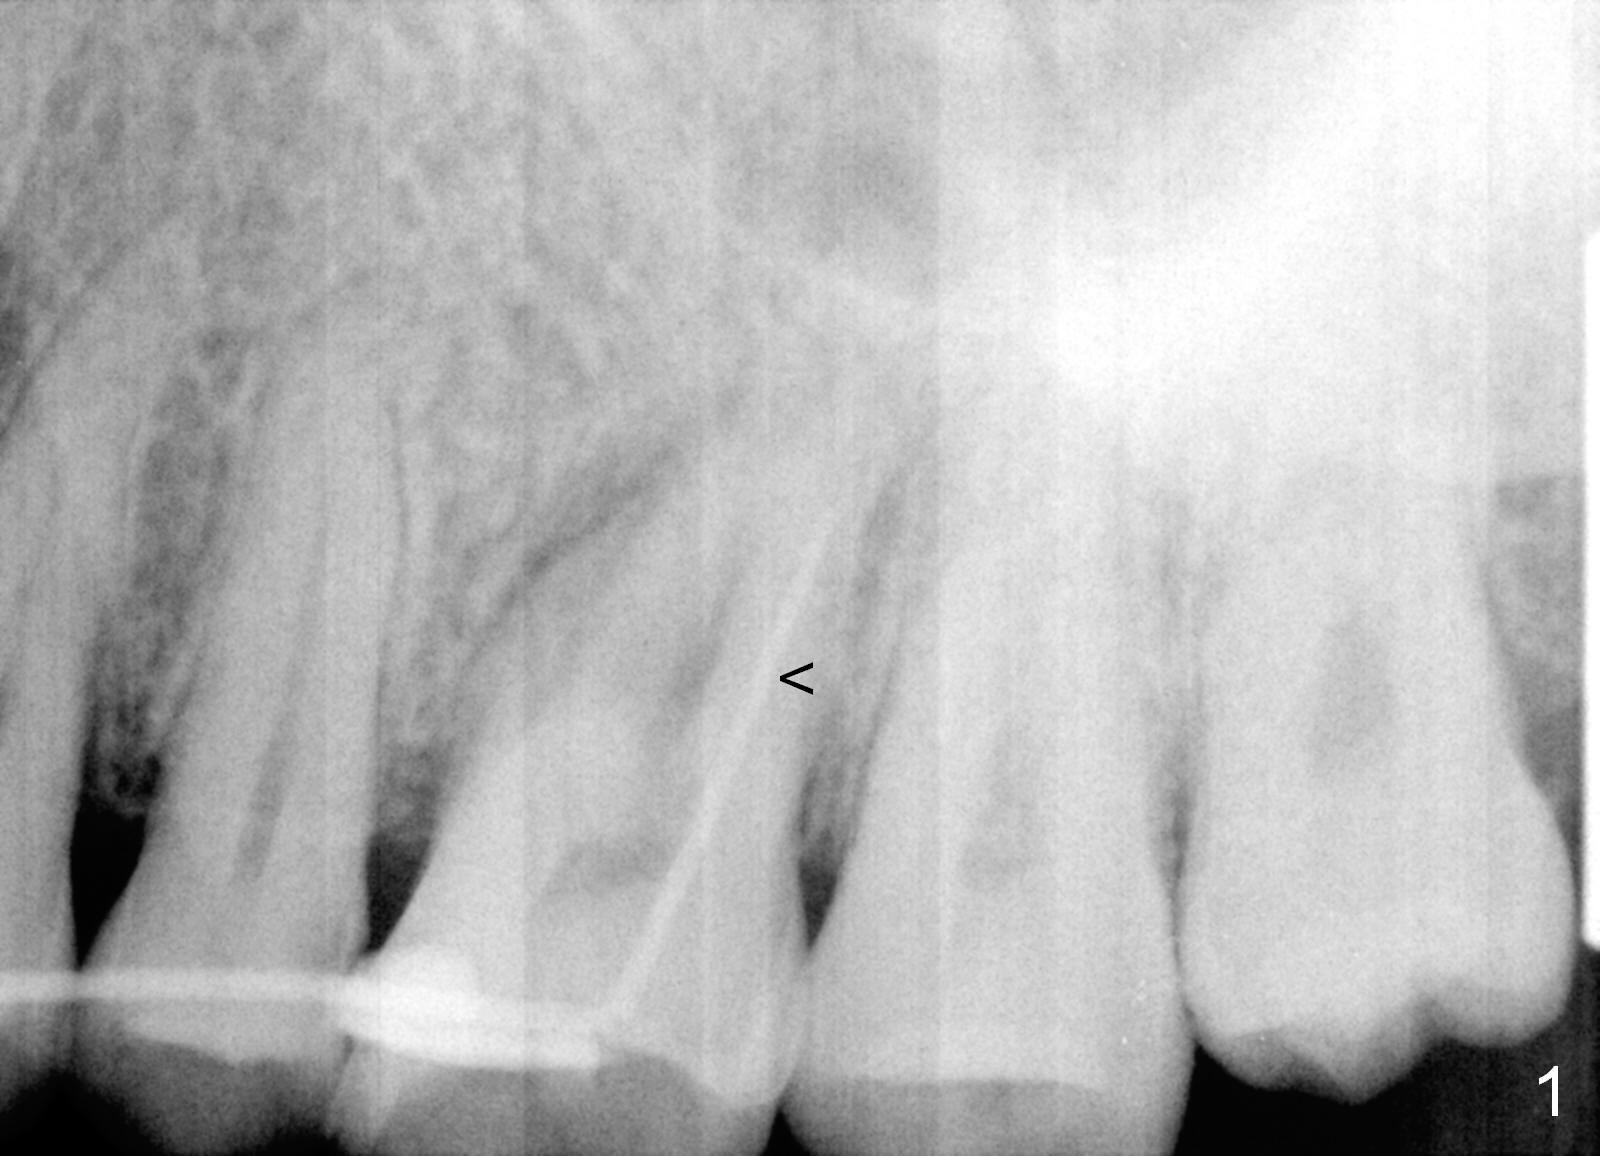

Bone Expansion at Septum

A 46-year-old woman has apical periodontitis with distal crack line at #14. There are 2 fistulae (buccal and palatal). A gutta percha is inserted into the buccal one (Fig.1 <). After extraction and Xylocaine gauze application in the socket, use 1.6 mm pilot drill in the septum for 7 mm, followed by Magic split and expanders for sinus lift. Place a relatively small implant (IBS, 4.5x13 or 5x11 mm, Fig.2) in the septum or a large one (6x13 mm or 6 mm 1-piece one, Fig.3) to obliterate the whole socket.